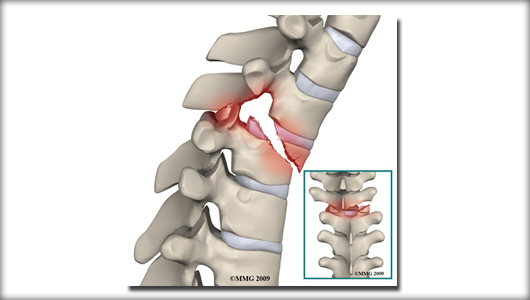

Spine fracture

spine-fracture

Fracture in the vertebral body disturbing the continuity in the alignment of back bones. Commonly occurs due to road traffic accident and fall from height...

Fracture in the vertebral body disturbing the continuity in the alignment of back bones is called as spine fracture. Commonly occurs due to road traffic accident and fall from height.

spine-fractures-intro

In simple fracture patient will have back or neck pain .In severe injury patient might have weakness of arms or legs.

Xray is the initial investigation . MRI and CT may be required dependin on the severity of the injury.

The treatment for simple fracture is rest and supportive appliances such as belt/ collar and orthosis. Complex fracture with displacement or with weakness might require surgery for stabilisation.